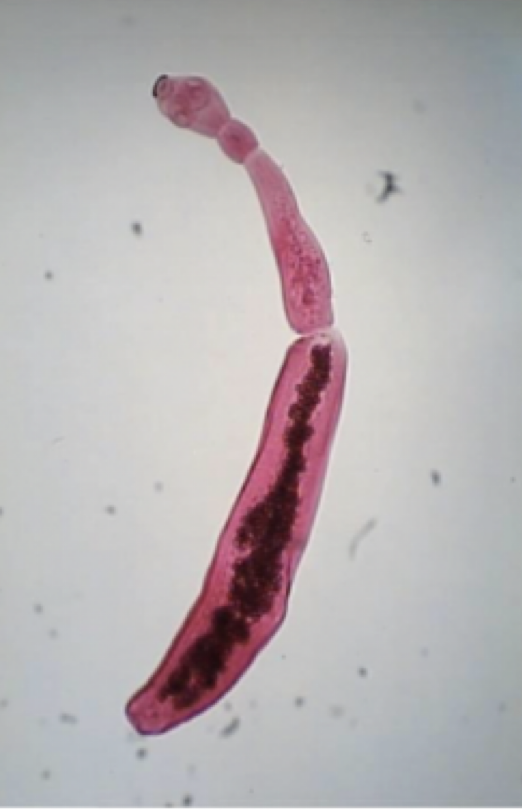

Diphyllobothrium latum

Mode of transmission: eat fish with cysticerci

Infective stage: Cysticerci

Host: D- human, I-fish

*common name: fish tapeworm

knowt flashcard image